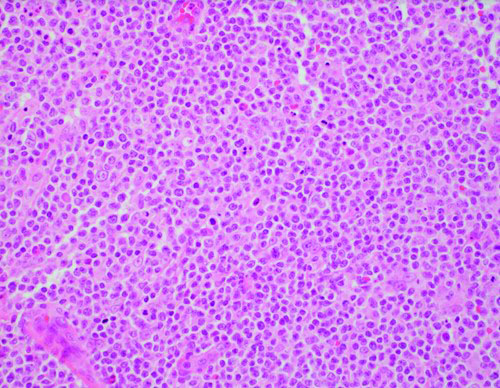

The LUL lesions were consistent with large cell transformation of MF. Histology showed diffuse infiltration of large atypical lymphoid cells from the basal epidermis to the deep margin in the deep dermis (Figure 2). There was focal epidermotropism with follicular mucinosis. Immunohistochemistry of the large cells showed CD3+, CD2+, CD4+, CD8−, CD30+, ALK−, P63−, granzyme-B+ in subset.

Figure 2: Histopathological slide of upper eyelid mass showing sheets of large atypical lymphoid cells. Hematoxylin and eosin. Magnification ×400.